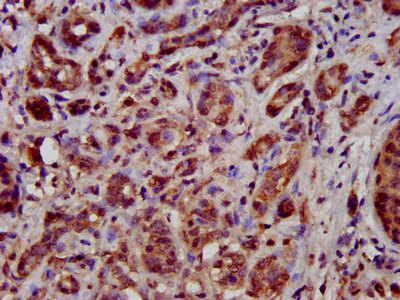

IHC image of CSB-PA023420LA01HU diluted at 1:500 and staining in paraffin-embedded human pancreatic cancer performed on a Leica BondTM system. After dewaxing and hydration, antigen retrieval was mediated by high pressure in a citrate buffer (pH 6.0). Section was blocked with 10% normal goat serum 30min at RT. Then primary antibody (1% BSA) was incubated at 4°C overnight. The primary is detected by a biotinylated secondary antibody and visualized using an HRP conjugated SP system.